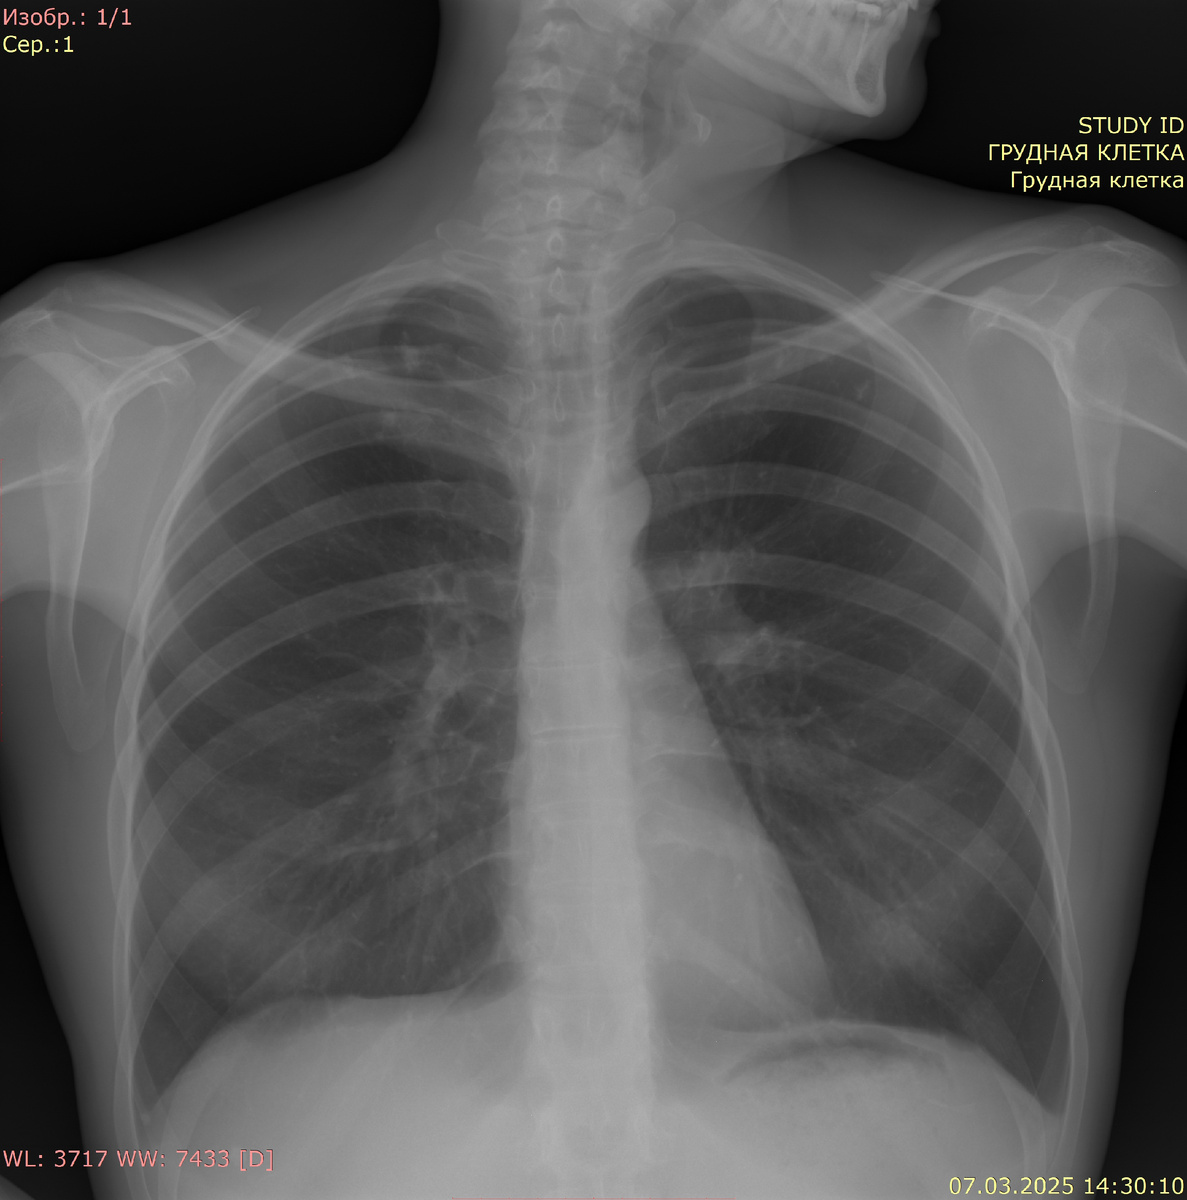

Рентгенография органов грудной клетки в прямой проекции:

Видимые дыхательные пути проходимы. Тень средостения не смещена, не расширена. Корни легких четкие, структурные, не расширены. В верхушках обоих легких очаговые тени до 5-8 мм. Синусы свободны. Костно-деструктивных изменений нет. Свободный газ не определяется.

Заключение: картина туберкулеза легких (уточнение анамнеза). Пневмонии нет